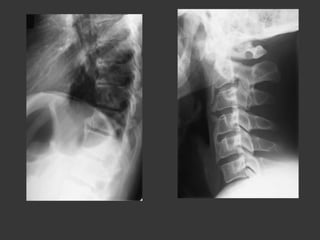

Roaccutane (isotrétinoïne):

8 months in 2007 and 4 months in

2010 !!!

Isotrétinoïne and bones

•  Sacroiliitis : seldom

*E. Eksioglu et al., Sacroiliitis and polyneuropathy during isotrtinoin treatment 2007

*Elias et al.,Acne fulminans and bilateral seronegative sacroiliitis triggered by isotretinoin 1991

*Bachmeyer et al., Isotretinoin induced bilateral sacroiliitis 2003

•  Diffuse Idiopathic Skeletal Hyperostosis like

Hyperostosis and calcification of tendons and ligaments

Bone bridges along the anterior longitudinal ligament (6

vertebrae at least)

*J. DiGiovanna et al., Isotretinoin effects on bone